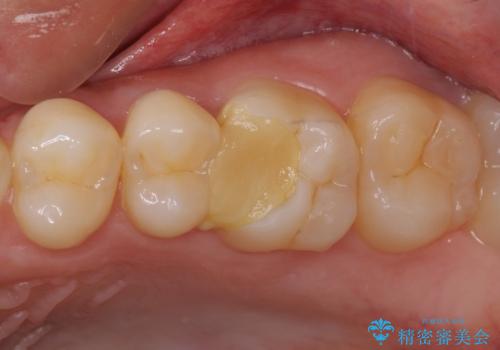

[根管治療・セラミッククラウン] 他院で抜くしかないと言われた歯の治療

![[根管治療・セラミッククラウン] 他院で抜くしかないと言われた歯の治療の症例 治療前](https://seimitsushinbi.jp/wp/wp-content/uploads/2021/01/91d1d4b8e73e8b08ee1f1a8d4bfa764d-500x350.jpg?v=1609913634)